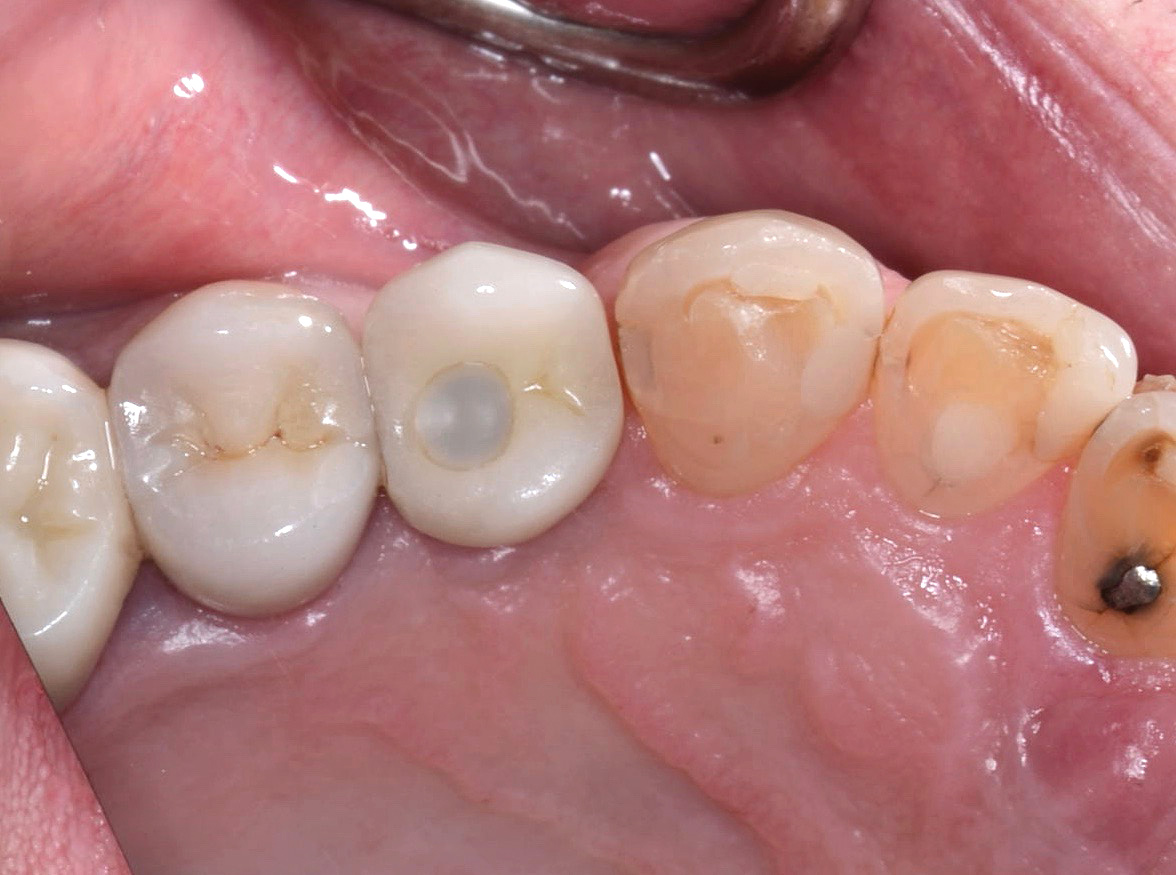

Fig 1. Chipping of veneering porcelain of porcelain-fused-to-gold full-arch fixed dental

prosthesis.

Figure 1

Fracture/Chipping of the Veneering Material

With 5-year complication rates from 3.2% to 25.5%,1 chipping of the veneering material (Figure 1) is the most common technical complication addressed in the literature.1,2 This can be minimized by designing the prosthesis before the final fabrication to ensure optimal framework design and thickness of the veneering material. Following basic occlusal principles in implant prosthodontics is essential. These include reduced cuspal inclination, narrow occlusal table, correction of load direction, reduced nonaxial loading, reduced length of the cantilever, and lighter occlusal contacts on implants.5 Restorations such as monolithic zirconia (Figure 2) and lithium disilicate are also being used to minimize chipping. However, long-term follow-up information on these restorations is limited.